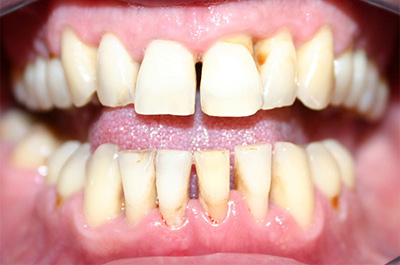

Диагностические мероприятия начинают с выяснения состояния зубов и дёсен, наличия аномалий, изменения цвета тканей, окружающих зубы.

Сначала прощупывают подчелюстные лимфоузлы, при наличии патологии они болезненные и увеличенные. Осматривают ротовую полость на наличие признаков заболевания:

- отёка и красноты дёсен;

- рыхлых краёв десны;

- карманов между десной и зубом;

- большого количества зубных отложений;

- расхождения между резцами;

- подвижности и открытых корней.